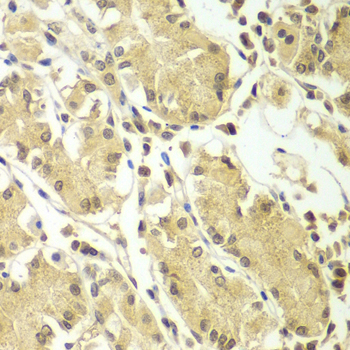

Immunohistochemistry of paraffin-embedded human kidney cancer using BCAS3 antibody at dilution of 1:100 (x400 lens).

Immunohistochemistry of paraffin-embedded human gastric using BCAS3 antibody at dilution of 1:100 (x400 lens).

Immunohistochemistry of paraffin-embedded mouse kidney using BCAS3 antibody at dilution of 1:100 (x400 lens).